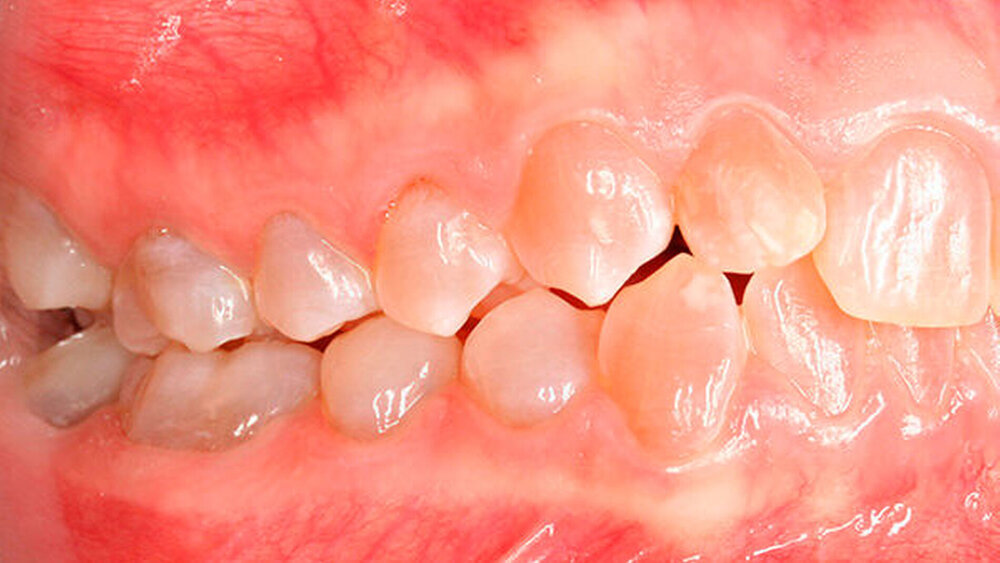

a) Dentinogenesis imperfecta. Da alle Zähne betroffen sind, ist von einer genetisch bedingten Fehlbildung auszugehen. Die Zähne der Patientin weisen zudem eine veränderte Farbe auf. Darüber hinaus sind Abplatzungen des Schmelzes vorzufinden. Trotzdem liegt keine Dentinogenesis imperfecta vor. Die Abplatzungen sind größtenteils geringfügig und zunächst oberflächlich, das heißt nicht unmittelbar bis zum Dentin. Die Farbänderung der Zähne entspricht nicht dem klassischen Bild einer Dentinogenesis imperfecta (siehe auch Abbildungen 3 und 4).

b) Erworbene Strukturanomalien: Da alle Zähne betroffen waren, ist von einer genetisch bedingten Ursache der Erkrankung auszugehen. Erworbene Strukturanomalien betreffen nur einzelne Zähne (Abbildung 5) oder Zahngruppen, die sich zur gleichen Zeit entwickeln [Übersicht in Feierabend 2014a]. In sehr seltenen Ausnahmefällen kann trotz genetisch bedingter Grundlage nur ein Teil der Zähne betroffen sein (Abbildung 6).